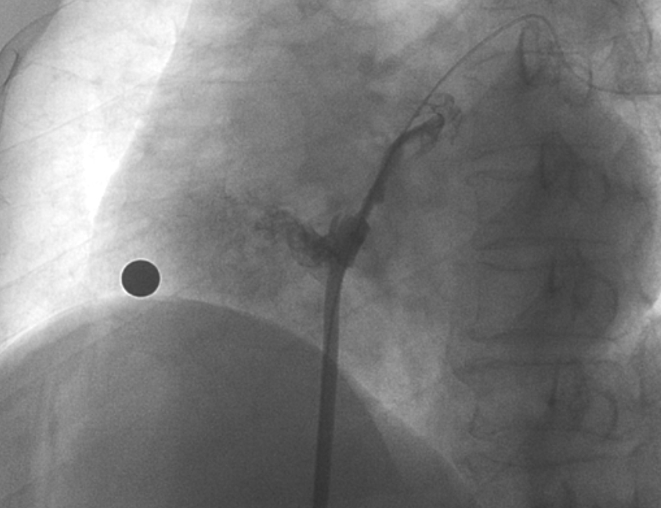

术中造影显示患者为PFO且长隧道型,目前市场上已商业化的PFO封堵器难以满足该患者解剖结构封堵需求。迪创医疗自主研发的OmniSeal PFO封堵器自适应性双盘贴合设计能广泛适应不同PFO隧道长度的解剖结构和形态,其双盘外包覆式阻流和隧道内填充阻流相结合的双重阻流设计,可为此患者实现有效封堵。与此同时,OmniSeal首创的完全可穿刺式设计,也为此患者最大程度地保留了房间隔区域穿刺通道,以实现全兼容未来可能的左心系统二次介入术。术终造影和心脏超声显示封堵完全、效果良好。作为OmniSeal的首例临床应用,本次手术的顺利完成和优异效果充分体现了产品的设计创新优势。

造影显示PFO封堵完全,无残余分流,

试验器械充分舒展并贴合良好